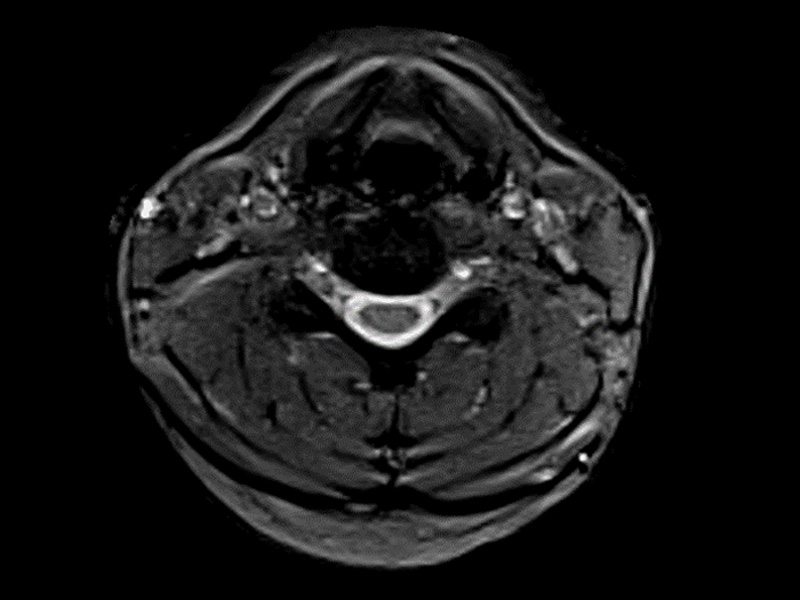

Klaustrofobní pacienti

Magnifico je ten správný systém pro klaustrofobické pacienty. Otevřený magnet z něj jednoduše dělá pohodlný zážitek z magnetické rezonance pro všechny pacienty, zejména děti. Magnifico navíc přichází s průhlednou hlavovou cívkou pro větší pohodlí pacienta.

Klinické snímky